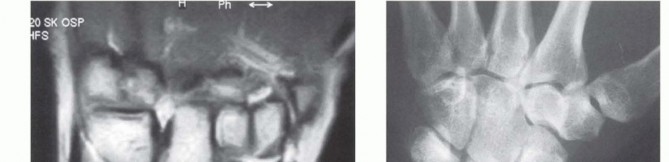

The natural history of Kienböck disease is one of progressive mechanical failure, reliably categorized by the Lichtman classification system. This staging is paramount, as it directly dictates our surgical algorithm. Stage I represents the earliest phase, where standard radiographs appear entirely normal, but magnetic resonance imaging (MRI) reveals the hallmark signs of ischemia: decreased signal intensity on T1-weighted images and variable signal on T2-weighted images, depending on the degree of reactive edema and attempted revascularization.

As the disease advances to Stage II, the lunate begins to exhibit increased radiodensity and sclerosis on plain radiographs. Despite these density changes, the overall anatomical shape and height of the lunate are maintained. This sclerosis represents a combination of compacted necrotic trabeculae and the apposition of new woven bone on dead trabecular cores—a frustrated attempt at creeping substitution. Stage IIIA, our patient's current stage, is characterized by structural failure. The lunate undergoes macroscopic collapse, losing its height and altering its geometry, yet the overall carpal height remains preserved, and there is no fixed scaphoid rotation or proximal migration of the capitate.

If left untreated, the condition relentlessly progresses to Stage IIIB, defined by lunate collapse accompanied by significant carpal instability. This includes a decrease in the carpal height ratio, proximal migration of the capitate into the space vacated by the collapsing lunate, and a fixed palmar flexion of the scaphoid, often visible as the "cortical ring sign" on AP radiographs. Ultimately, the altered kinematics lead to Stage IV, characterized by widespread radiocarpal and midcarpal secondary osteoarthritis. Our goal with the radial shortening osteotomy today is to intercept this natural history at Stage IIIA, preventing the catastrophic transition to Stage IIIB and Stage IV.

Clinical & Radiographic Imaging Archive